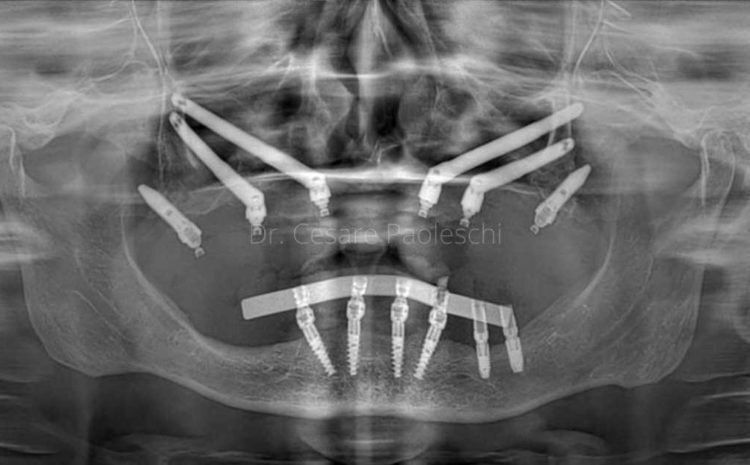

Gli impianti zigomatici sono una soluzione idonea alla riabilitazione di casi complessi con gravissima atrofia del mascellare.

FASE 2 - Studio del repertorio radiologico (Tac – Panoramica – Radiografia) e della stereolitografia

Il relatore: Dott. Cesare Paoleschi